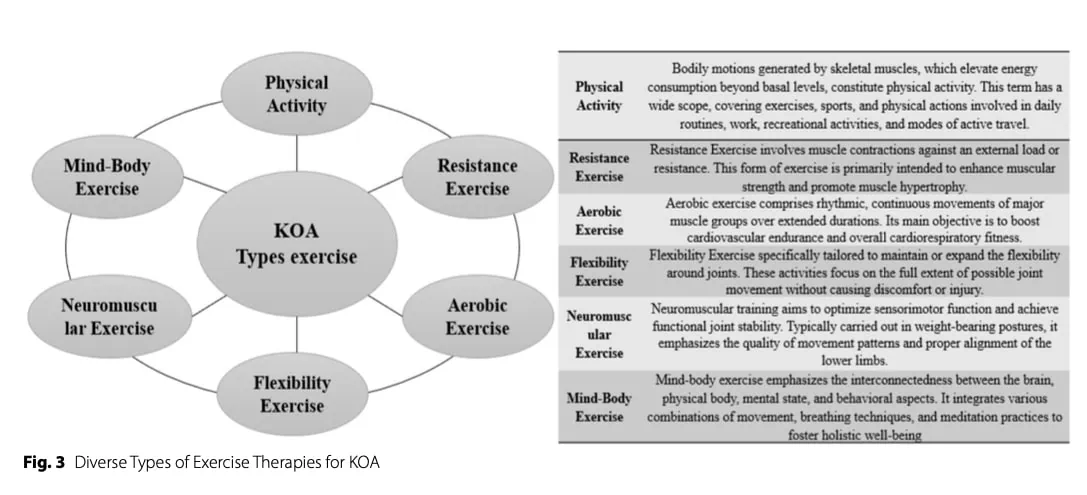

保守治疗被广泛认为是膝关节骨性关节炎康复的一线治疗方法。 膝关节骨关节炎康复的一线治疗方法。尤其是在全球骨关节炎发病率不断上升的背景下,预计到 2050 年,发病率将增加 74%。 以运动为基础的干预措施--包括阻力训练、活动度和柔韧性练习、有氧调节以及针对协调、平衡、本体感觉和神经肌肉控制的特定任务训练--在减轻疼痛、改善身体功能和肌肉力量方面一直都很有效。

运动在骨关节炎中的作用

膝关节骨关节炎通常与关节源性肌肉抑制有关,导致功能损害,尤其是在行走时。 运动疗法在减少肌肉抑制、恢复肌肉力量和步态正常化方面发挥着核心作用。

虽然最初认为运动对关节软骨的结构没有直接影响,但新出现的证据表明,运动可能会对滑液循环产生积极影响,从而促进软骨营养输送和废物清除。 这些生理性作用可能有助于减少接受常规运动疗法的患者体内的炎症标志物,即使在软骨结构没有明显再生的情况下也是如此。

尽管有强有力的证据支持锻炼可缓解症状,但膝关节骨关节炎康复的最佳锻炼方式和进展策略仍未完全明确。

有氧运动

运动方式

由于步态周期和游泳等低冲击有氧运动对关节的负荷较小,因此传统上推荐这类运动。 然而,新出现的证据表明,对于膝关节骨关节炎患者而言,只要对症状进行适当监测并循序渐进,跑步等冲击性较强的活动并不一定会增加膝关节结构性损伤。

阻力训练

运动方式

阻力训练可从明显疼痛或抑制情况下的等长收缩练习开始,然后进展到针对股四头肌、腘绳肌和臀肌的动态、多关节强化练习。

从临床角度看,运动似乎主要通过症状调节和功能改善而非直接软骨再生来发挥作用。 综述文献表明,水上运动在康复的早期阶段尤其有助于减轻疼痛和改善运动范围,从而促进患者的参与。 随着症状和活动度的改善,陆上运动往往能在减轻疼痛和提高功能方面带来更大的益处,这可能是由于对机械和神经肌肉的要求更高。

- 运动处方应遵循 FITT 框架(频率、强度、时间、类型),并以患者的功能、症状和反应为指导。 结合 有氧运动、阻力运动、神经肌肉运动、平衡运动和活动度运动的组合能带来最大益处。 最初可进行水中运动,随着耐受性的提高再过渡到陆上运动(Physiotutors 关于 KOA 运动的视频)。Physiotutor KOA 运动视频).